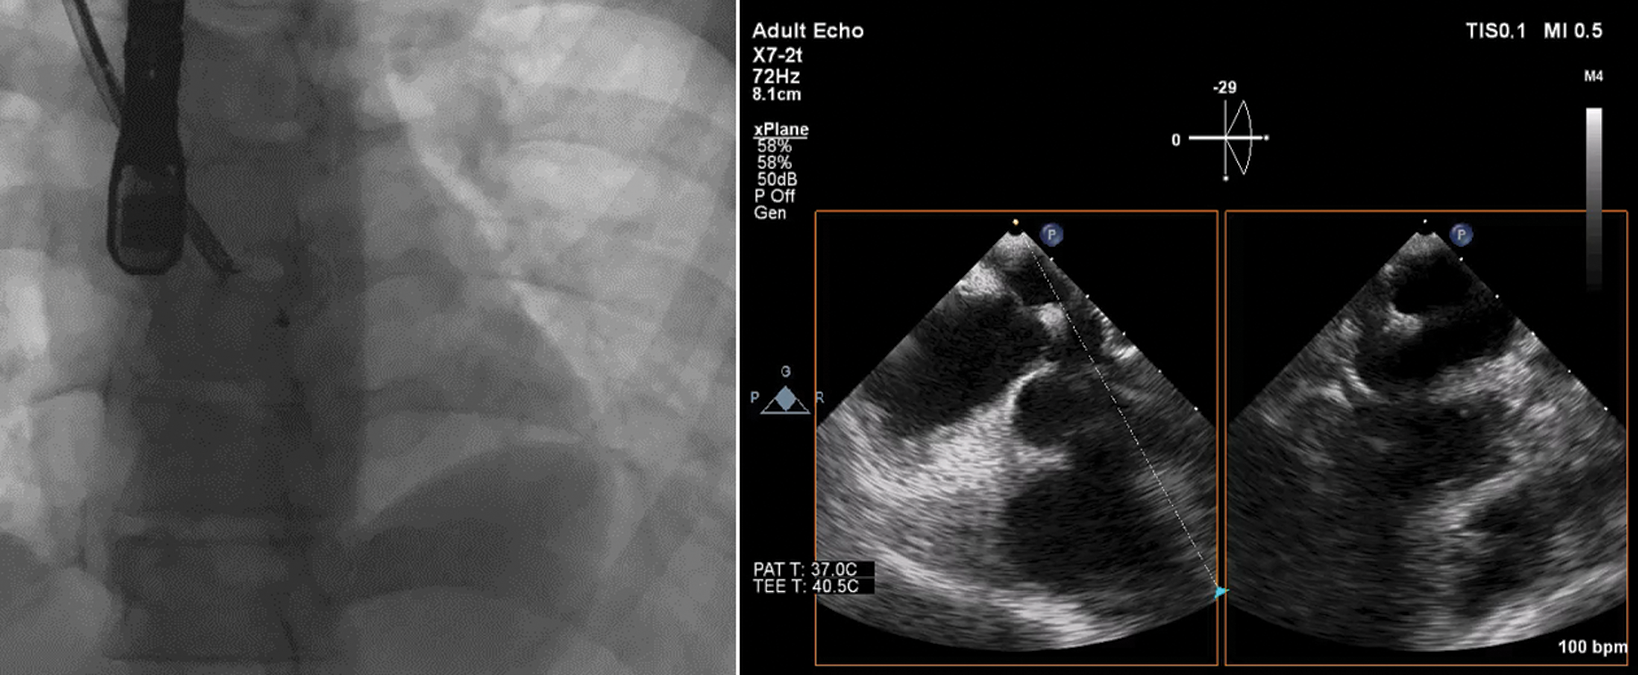

After gently withdrawing the LA disc towards the left side of the interatrial septum, the RA disc was released on the RA side. Proper alignment of the device with captured rims and no residual flow was confirmed on TEE before releasing of the device (Fig. 5). The procedure was completed without any complications with a slightly longer procedural (50 min) and fluoroscopy time (7.5 min).

Figure 5: Fluoroscopy (left panel) and transesophageal echocardiography (right panel) images showing in situ and well-seated occluder device